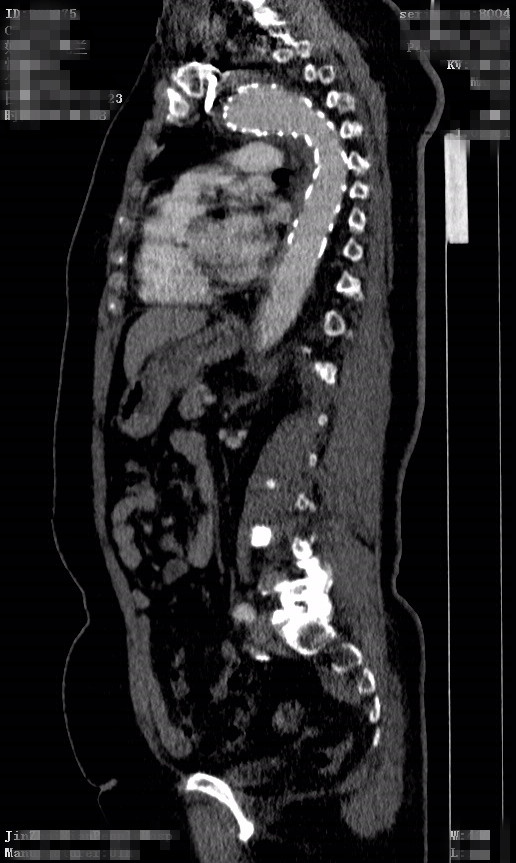

患者王某某,女性,66岁,无明显诱因下出现胸腹部不适,几日后患者自觉疼痛加重,起初未予重视,后疼痛无明显好转,来我院就诊。查胸部CT示:1、左心室增大。2、主动脉增宽,附壁血栓?主动脉夹层待排,建议CTA检查。3、双侧胸腔少量积液。胸腹部主动脉增强CT示:1、主动脉夹层。2、双下肺炎症。3、左侧胸腔积液。4、左心室增大,考虑高心病。入我院外周介入科拟"1.主动脉夹层;2.高血压病2级(极高危组);3.冠心病"收治入院。

入院后给予稳定血压、镇痛等对症治疗。近日,在全麻下行“左上肢动脉、主动脉造影+右股动脉切开+胸主动脉夹层覆膜支架腔内隔绝术”术前主动脉造影示:主动脉大弯侧见龛影,距左锁骨下动脉开口约1cm术后行主动脉造影示:主动脉弓大弯侧龛影消失,左锁骨下动脉显示良好,支架周围未见内瘘。患者术后十天复查支架位置良好。